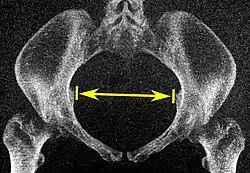

| Diâmetro intertuberositário |

![]() Plano axial |

Os pontos ósseos mais próximos das tuberosidades isquiáticas | 10 a 12 cm.[6] | |